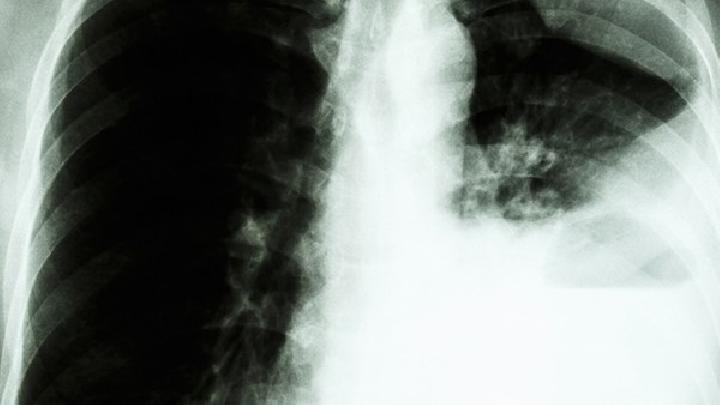

很多人由于工作环境的关系,长时期在充满粉尘的环境中,这样长期下去,便引起了尘肺病,这是一种肺部疾病,是由于吸入的粉尘太多造成的,为了使大家远离尘肺病,下面来给大家介绍一下怎么预防尘肺病。